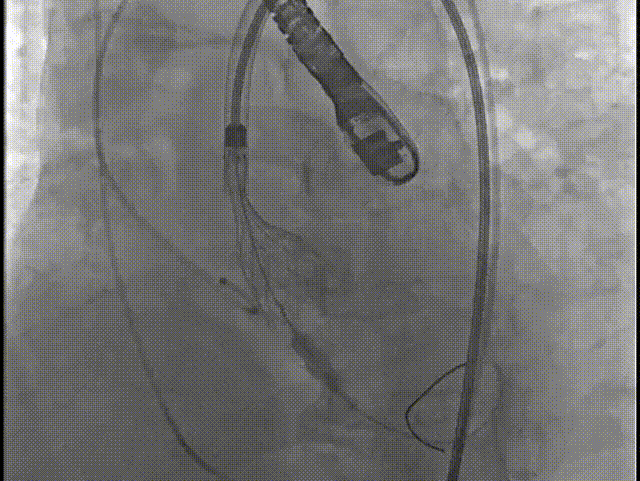

6.根据术前评估及球囊预扩情况,选择23mm沛嘉TaurusElite瓣膜进行植入,在150次/分保护起搏下0位释放瓣膜;

7.造影评估示瓣膜植入深度、工作形态良好、微量瓣周漏,遂予以全部释放;

10.后扩完毕,撤出猪尾导管,造影示瓣周漏改善,手术圆满成功;